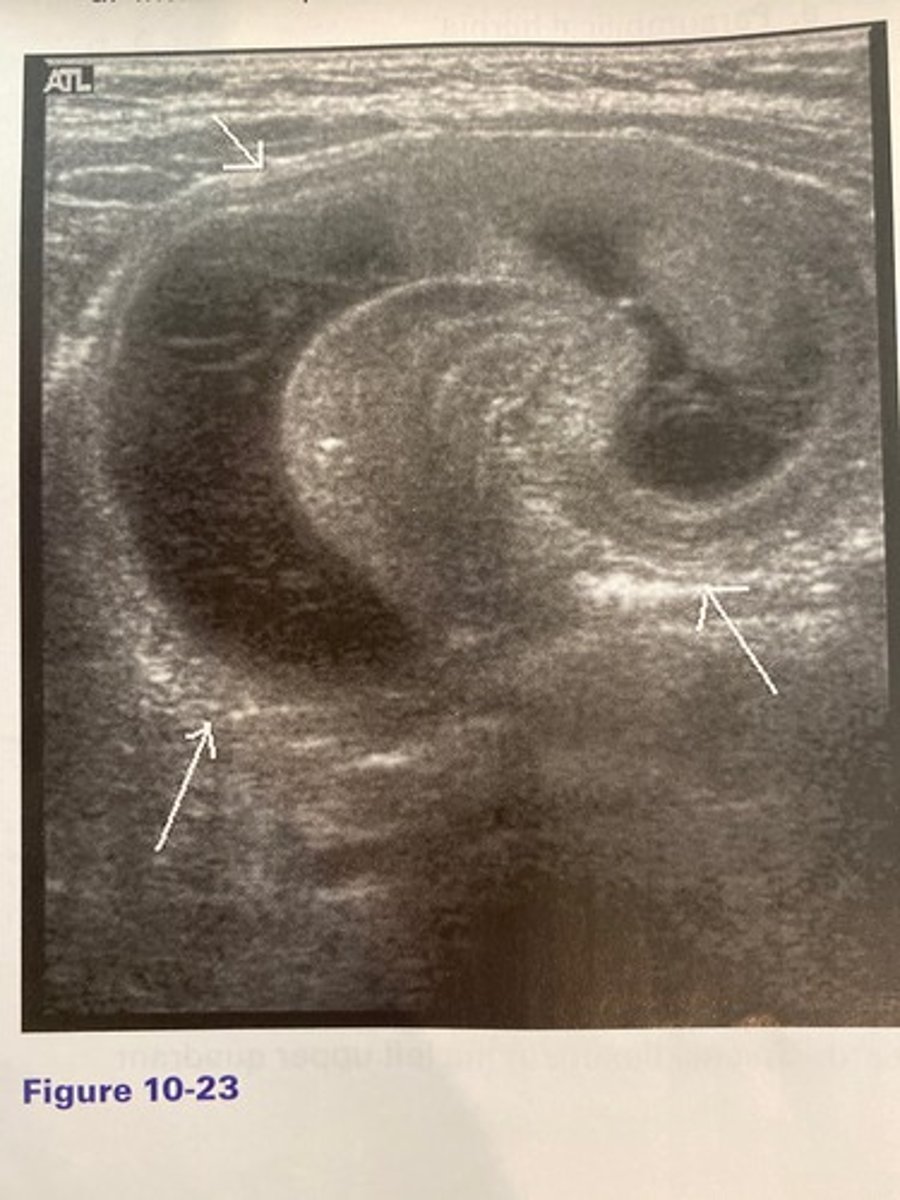

d. Intussusception

The finding in Figure 10-23 was discovered in the right lower quadrant of an 18-month-old patient with a history of intermittent, severe abdominal pain, and vomiting. What is the most likely diagnosis?

a. Appendicitis

b. Colitis

c. Mechanical obstruction